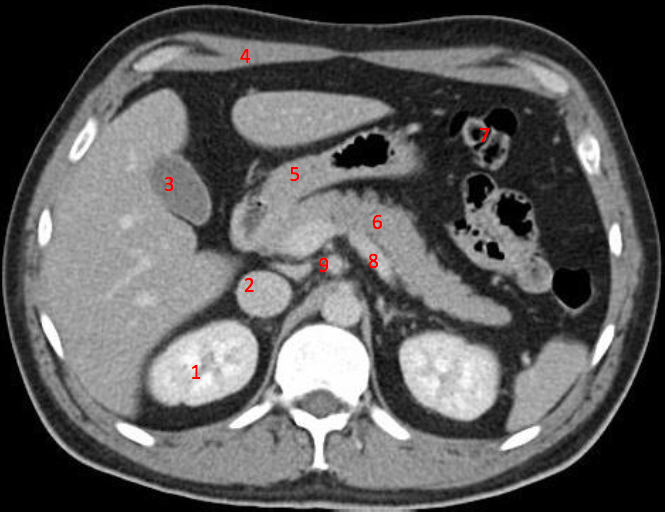

Number 1?

R Kidney

Number 2?

IVC

Number 4?

Head of pancreas

Number 7?

Bowel (probably large)

Number 6?

Stomach

Number 5?

Rt ureter

Descending colon

Number 9?

Superior mesenteric artery